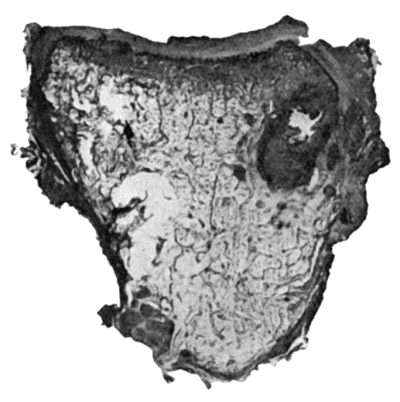

| 114. | Section through Gouty Bursa | 428 |

| 115. | Tuberculous Disease of Sub-Deltoid Bursa | 429 |